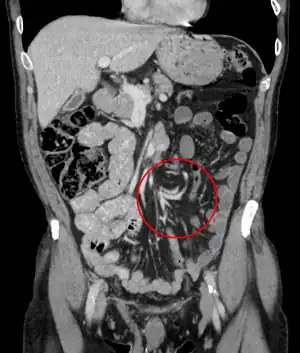

Coronal CT of the abdomen, demonstrating a volvulus as indicated by twisting of the bowel stock

A volvulus is when a loop of intestine twists around itself and the mesentery that supports it, resulting in a bowel obstruction.[1] Symptoms include abdominal pain, abdominal bloating, vomiting, constipation, and bloody stool.[1][2] Onset of symptoms may be rapid or more gradual.[2] The mesentery may become so tightly twisted that blood flow to part of the intestine is cut off, resulting in ischemic bowel.[1] In this situation there may be fever or significant pain when the abdomen is touched.[2]

Risk factors include a birth defect known as intestinal malrotation, an enlarged colon, Hirschsprung disease, pregnancy, and abdominal adhesions.[1] Long term constipation and a high fiber diet may also increase the risk.[3] The most commonly affected part of the intestines in adults is the sigmoid colon with the cecum being second most affected.[1] In children the small intestine is more often involved.[5] The stomach can also be affected.[6] Diagnosis is typically with medical imaging such as plain X-rays, a GI series, or CT scan.[1]